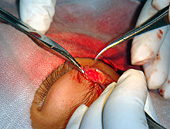

Dr. Gupta operating on 2-year old girl.

Exposure of cavity after cyst removal.